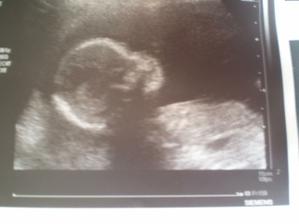

30.03.2010 těhu potvrzeno, jsem v 7tt a z utz na mě kouká "jen" takový malý hrášek, manžílek tomu konečně věří a prožívá to víc než já 🙂

kontrola byla ok, vše v pořádku, svišť má 2,5 cm, jsem v 9+1tt

06.05.2010 konečně dostávám průkazku, máme první fotečku, svišť má 8 cm, jsem ve 13tt. Při ultrazvuku jsem se strašně moooc nasmála, protože pani doktorka chtěla sviště vyfotit v co nejhezčí poloze a jak ho naháněla, tak on se "bránil", mrskal sebou, kopal, házel rukama, až jsem se divila, jak je tak malý drobeček pohyblivý a aktivní, má zatím dost místa, tak řádí. Od doktorky odcházím plná dojmů a šťastná!!!!!!!!! Manža je pyšný.

22.06.2010 21.30h jsme po velkém ultrazvuku a konečně víme, co čekáme. Je to kluk jako buk. Je v pořádku, slyšeli jsme srdíčko, viděli mozečeka ručičiky, no prostě všechno, má 22 cm a 250 g, takže takový drobeček. Jsme šťastní!!!!!!!!!!!!!!!!!!!!!!!!!!

06.09.2010 poslední ultrazvuk ve 31tt a odběr krve - kontrola byla ok, prcek ještě hlavičkou dolů není, ale ještě máme čas